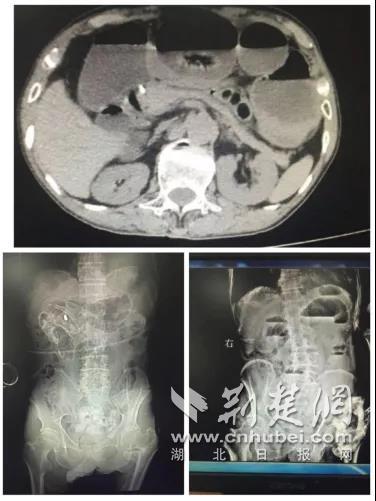

老人曾有两次手术史,一年前因脑梗塞导致左上下肢偏瘫,同时合并高血压,肺气肿,生活不能自理。入院时查体:急性重病容,消瘦,腹部隆起有肠型有压痛,肠鸣音亢进,可闻气过水音,左上下肢活动障碍。腹部CT提示肠梗阻,常规必须手术治疗,但患者体质差,又合并其他严重疾病,不宜手术,保守治疗近一周无效果。

患者家属同意后,在DSA机器引导下,经鼻置导管入肠腔行梗阻肠管球囊扩张、引流留置导管等处理,并给予中药、补液、对症、支持治疗,在护士团队精心护理下,次日患者肛门排气排便,腹疼腹胀症状消失,24号复查腹部CT提示肠梗阻解除,现患者恢复饮食,病情转危为安,避免了手术风险及创伤的痛苦。